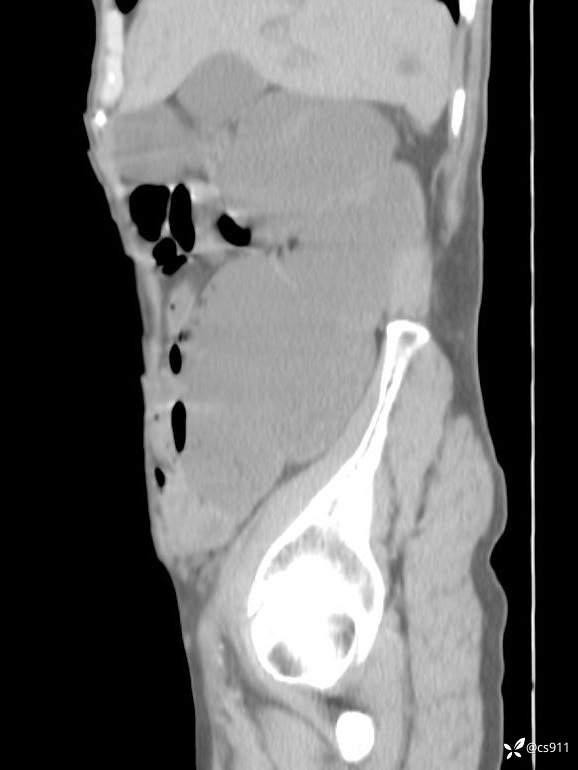

急腹症之急诊CT,原因?答案公布

男,77岁,腹痛、腹胀伴恶心呕吐1天。呕吐胃内容物,非喷射性呕吐,有咖啡色样胃内容物,诉有胃穿孔病史。查体:全腹平,下腹部压痛,全腹无反跳痛,叩诊呈浊音,移动性浊音阴性,肠鸣音减弱,1-2次/分。肛检:直肠未扪及明显肿物,可触及大量粪块。

T 36.6℃ P 80次/分 R 26次/分 BP 100/60mmHg

白细胞(WBC) H 14.55 10e9/L 4-10

中性粒细胞百分率(NEUT%) H 85.7 % 40-75

血淀粉酶(AMY) HH 1859 U/L 35-135

癌胚抗原(CEA) H 27.44 ng/ml 0-5

呕吐物 潜血试验 * 阳性 阴性

患者轮椅入室检查神志清楚, 能配合摆位和呼吸